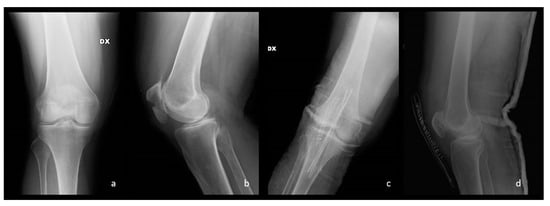

Figure 7.

In (a,b) preoperative anteroposterior and latero-lateral views of a patellar fracture that occurred in a 66-year-old lady. In (c,d) post-operative radiographs.